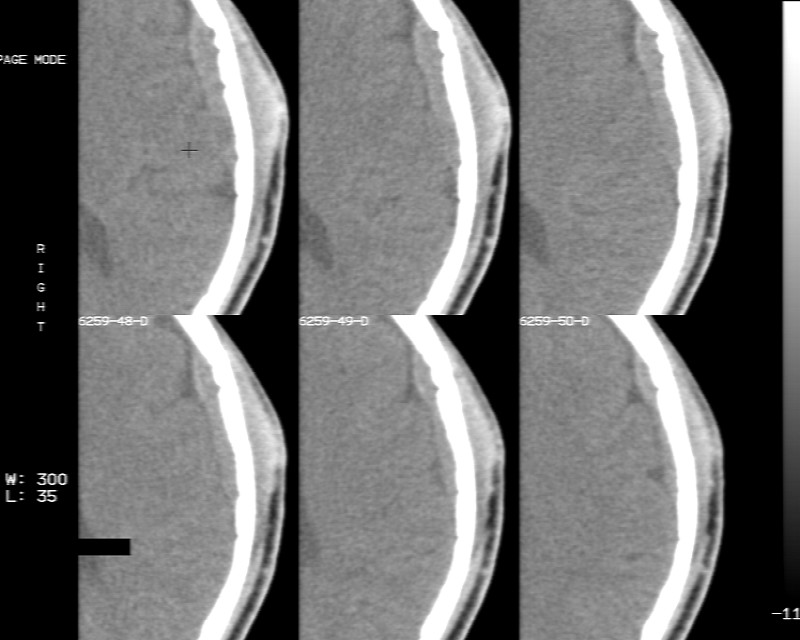

m70y, 2个月前发现左颞部有'包'隆起,近来自觉增大,无外伤无任何不适症状而就医,触诊包块质地较硬无移动无波动无皮温升高,胸片示右上肺陈旧结核....,ct扫描见左颞骨翼板局部内外骨板骨质破坏,似筛孔状,外板侧有骨膜线状增生,伴局部软组织丘状肿块,内板下梭形肿胀硬膜增厚翘起......颅内脑无异常.考虑骨良性病变 1.低度骨感染.   2.嗜酸性肉芽肿. 3.不排外骨结核...建议其穿刺活检,但患者失踪,追踪到结果定将公告.请大家分析.

左颞骨内板不光滑,密度减低,内板下可见新月形的软织密度影。脑实质轻度受压,外板外见膨胀形稍高密度影。考虑嗜酸性肉芽肿。建议增强扫描

骨质密度不均,骨质两旁均有软组织影,考虑嗜酸性肉芽肿可能性大,同时也不能除外转移瘤。

除了以上的诊断,大家不考虑转移瘤吗,病人有陈旧结核,合并瘢痕癌呢,并发颅骨转移,肺癌发生骨转移的几率要比其它恶性肿瘤大的多,虫蚀样的骨质破坏就是良性病变吗,我考虑转移瘤。